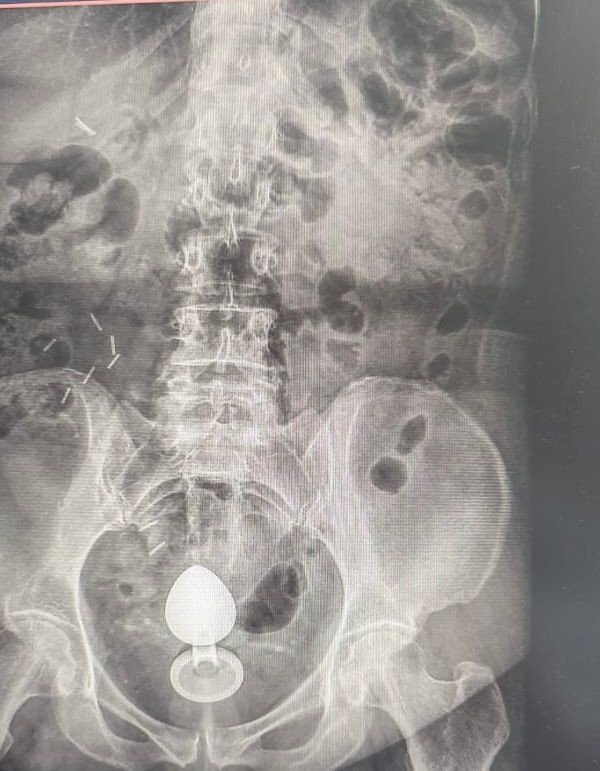

Raio-x mostra paciente com plug anal “sugado” pelo intestino

O caso foi atendido pelo cirurgião coloproctologista Daniel Brosco. Segundo o médico, a paciente contou que, na verdade, estava usando o sex toy para ajudar com a constipação intestinal, e não com finalidade sexual. O médico alerta que isso é contraindicado.

“A paciente contou que colocou o objeto no ânus por volta das 7h. Pouco mais de duas horas depois, ao sentar, percebeu que ele tinha subido e precisou buscar atendimento médico”, explica o médico.

🔴 Como isso acontece? O intestino pode “sugar” esses objetos por causa dos movimentos peristálticos — contrações involuntárias responsáveis pelo funcionamento do órgão — ou pelo vácuo criado em áreas como o reto.

O médico explica que a paciente tinha um quadro de pólipos no intestino — quando a mucosa apresenta um crescimento anormal que pode evoluir para câncer. Com isso, a parede intestinal era mais sensível, aumentando o risco de perfuração.

Brosco afirma que ela passou pelo procedimento para retirada do objeto e passa bem, mas que o caso é um alerta sobre o uso desse tipo de brinquedo. O uso inadequado pode levar a complicações como lacerações, sangramentos e perfurações intestinais — especialmente em pacientes com condições prévias que tornam a mucosa mais sensível.